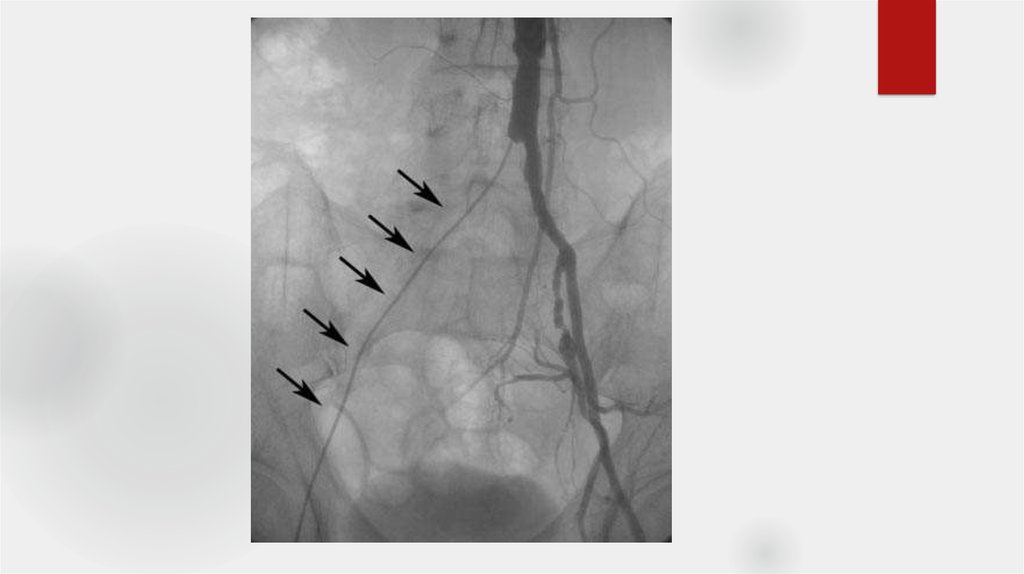

24. Оценка ангиограмм

Критерии:

- Окклюзии, их локализация

- Сегментарный уровень

- Степень

- Длинна пораженного участка

- Конфигурация и анатомия

- Количество пораженных артерий

- Морф.тип стеноза

- коллатеральное кровообращение